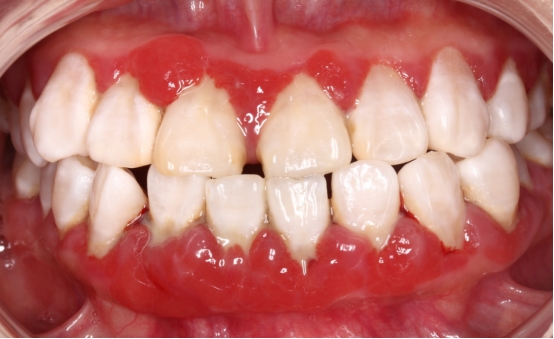

反复的牙龈肿痛溢脓

有些患者牙龈反复“长包”,并且有黄色的脓液流出,这就是牙周炎症导致的“牙周脓肿”。